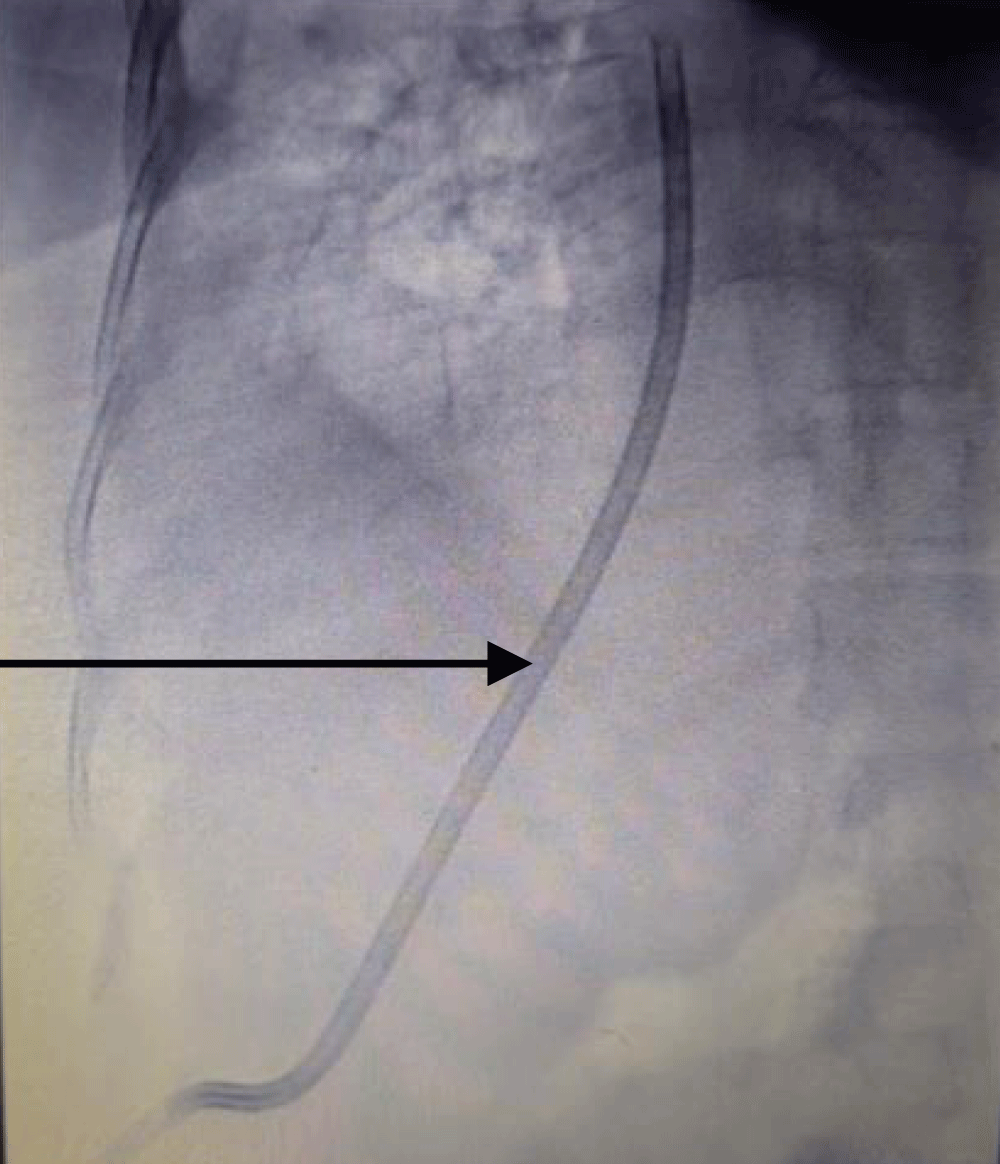

The patient was taken to the cath lab where the procedure was done under ultrasound and fluoroscopy guidance. The procedure was done with a sterile technique and using anti-septic measures; in the cath lab. After cleaning and draping the abdomen, first the right hepatic vein was visualized via ultrasound, and it was punctured by a Chiba needle via the percutaneous route. A guide wire was passed and its position was traced by ultrasound (Figure 1) and fluoroscopy (Figure 2). Radial artery sheath and Kumpe catheter were used as needed to negotiate guide wire in the inferior vena cava and right atrium. A subcutaneous tunnel of 5 cm was created and a tunnelled dialysis catheter was pulled through it (Figure 3). Contrast was injected into the sheath to visualize its flow. The contrast was seen flowing in the right atrium confirming the correct position of the sheath and the kumpe wire (Figure 4). The guide wire was then reinserted into the sheath. As the guide wire reached the inferior vena cava, it was negotiated to the right atrium. This was followed by the removal of the sheath and kumpe wire. After confirming the position of the guide wire in the right atrium (Figure 2), sequential dialation of the tract was done by dilators 6 fr, 8 fr, 10 fr, 12 fr, 14 fr, and finally 14.5 Fr x 19 cm trans-hepatic tunneled dialysis catheter was secured along with subcutaneous tunnel (Figures 5,6). The catheter tip was kept at the junction of the right atria – inferior vena cava (Figure 5). Ultrasound of the liver was done to rule out haemorrhage. There was slight post-operative pain post catheter insertion which subsided after a while. She was kept in the intensive care unit for a day for monitoring of vitals and was moved to the ward the next day. The procedure was uneventful. After being discharged, the patient underwent multiple sessions of hemodialysis with this access. She was told to take proper hygiene care of the area where the catheter was inserted to prevent catheter-related bloodstream infections. She once had an upper respiratory tract infection following which she had poor flow from the tunneled trans-hepatic dialysis catheter. She underwent repositioning of the catheter in the cath lab following which good flow was achieved. She was explained to avoid forceful coughing which can displace the catheter from its position; hampering the flow.

Figure 3: Image showing a part of tunneled dialysis catheter being in a subcutaneous tunnel before final insertion.